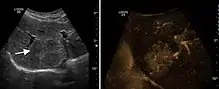

Liver cyst

Hydatid liver cyst. Diagnostic criteria are the presence of membranes and sediment inside.